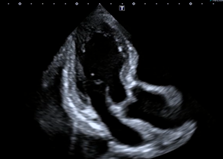

心臓